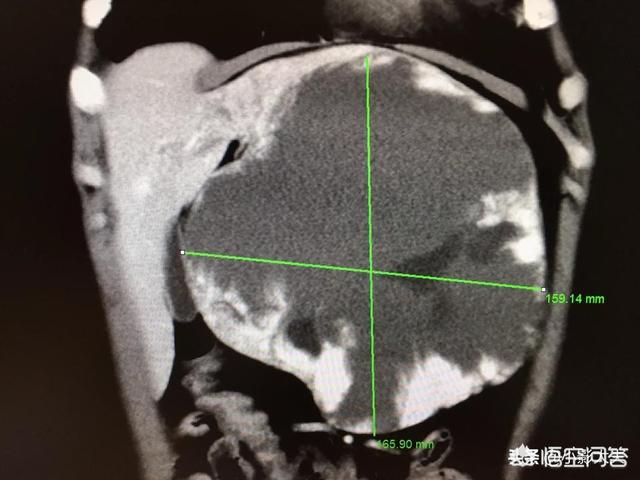

- Die CT der Leber kann sowohl die Anzahl als auch die Größe von Leberhämangiomen deutlicher zeigen und ist dem Leberultraschall überlegen.Bei Patienten, bei denen im Leber-Ultraschall hepatische Hämangiome festgestellt wurden, kann eine weitere CT-Untersuchung der Leber durchgeführt werden, um die Anzahl, Größe und Lage der Hämangiome usw. zu klären, insbesondere eine erweiterte CT-Untersuchung der Leber, um die Diagnose zu klären.

Bei der obigen Aufnahme handelt es sich um ein CT-Bild eines Leberhämangioms mit einem Schatten geringer Dichte im rechten Leberlappen mit klaren Rändern und progressiver Anreicherung vom Rand zur Mitte nach der Anreicherung.

Unten ist das größte hepatische Hämangiom, das ich je gesehen habe, 16 cm groß, 54-jährige Frau, die wegen epigastrischer Schmerzen behandelt wurde.

Große Hämangiome sind solche, die größer als 5 cm sind und Symptome aufweisen, die mit einer erheblichen Kompression einhergehen, wie z. B. Schmerzen in der Leberregion, Leberfunktionsstörungen und Hämangiome am Rand der Leber. Weibliche Patienten wie die oben genannte, die Symptome haben und 16 cm groß sind, müssen aktiv behandelt werden.